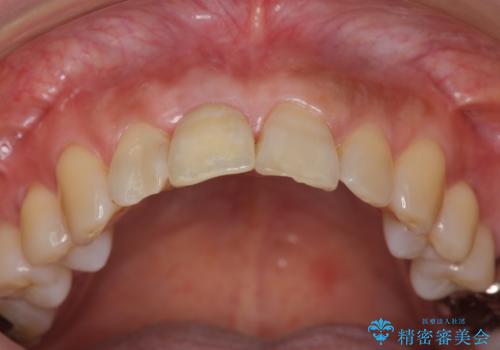

前歯のインプラント治療は適切に行えば、ブリッジのように隣の歯を削らずに審美的で機能的な状態に仕上げることが可能です。

インプラント周囲に十分な骨や歯ぐきの厚みの整備を行うことで、審美的なインプラントの仕上がりを達成することができます。